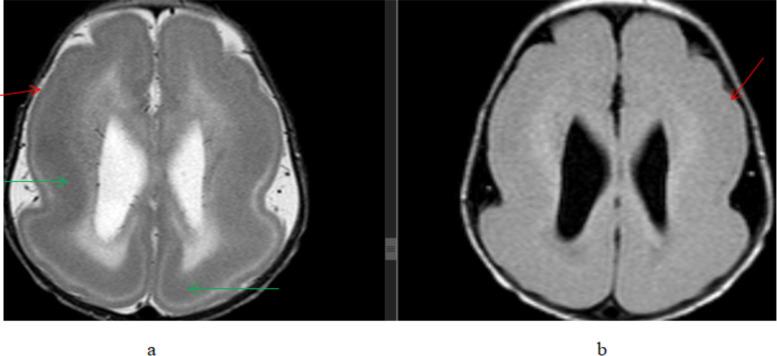

A total of 164 patients were included in this study of which 95(57.9%) were male and 69(42.1%) female patients were seen. A total of 120 patients (73.2%) showed abnormal brain MRI studies. Previous neurovascular insults were the most common abnormalities seen in 75(45.7%) patients followed by imaging findings of congenital and developmental abnormalities seen in 20(12.2%) patients.

本研究共纳入 164 例患者,其中男性 95 例(57.9%),女性 69 例(42.1%)。共有 120 例(73.2%)患者的脑部 MRI 检查结果异常。最常见的异常是既往神经血管损伤,见于 75 例(45.7%)患者,其次是先天性和发育性异常的影像学表现,见于 20 例(12.2%)患者。